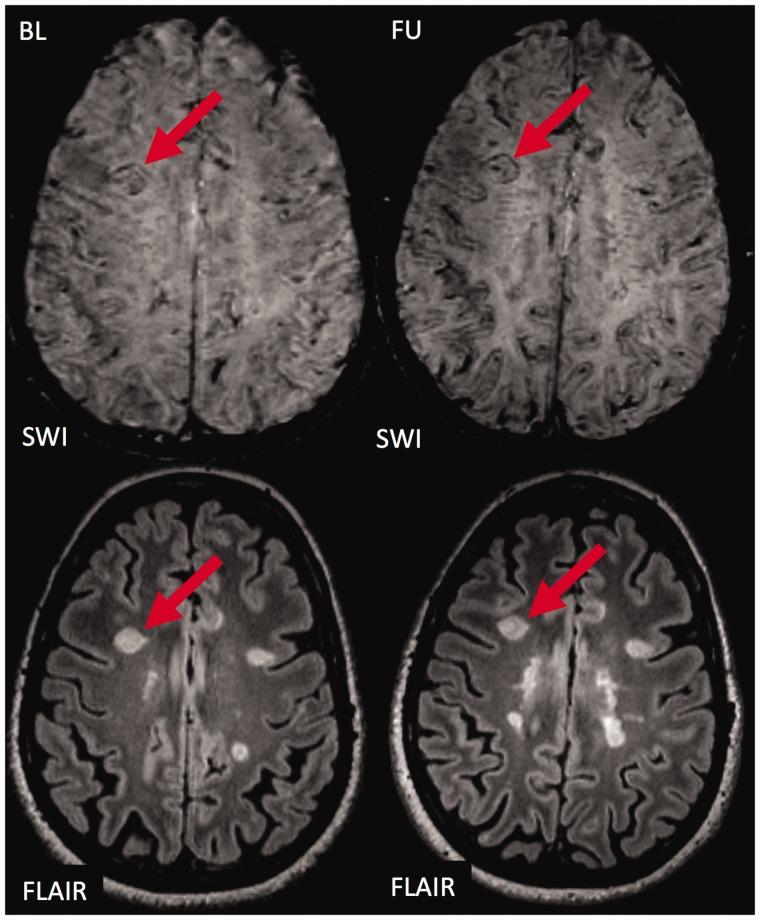

Brain lesions with a hypointense ring or core were described in multiple sclerosis on susceptibility weighted imaging.

The purpose of this study was to study the evolution and prognostic relevance of susceptibility weighted imaging hypointense lesions in clinically isolated syndrome and early multiple sclerosis.

Sixty-six early multiple sclerosis and clinically isolated syndrome patients were followed over a median period of 2.9 years (range 1.6-4.6 years) and underwent 3T magnetic resonance imaging including 3D susceptibility weighted imaging and T2-weighted fluid-attenuated inversion recovery. We assessed the presence of susceptibility weighted imaging hypointense core or ring lesions, and Expanded Disability Status Scale at baseline and follow-up.

Of 611 lesions at baseline, 64 (10.5%) had a susceptibility weighted imaging hypointense core, and 28 (4.6%) had a susceptibility weighted imaging hypointense ring. Hypointense ring lesions were larger ( < 0.001) and more T1w hypointense ( = 0.002) than others. During follow-up, hypointense core lesions became susceptibility weighted imaging isointense (52 lesions, 81%); few developed into hypointense ring lesions (two lesions, 3%). Hypointense ring lesions did not shrink on T2-weighted fluid-attenuated inversion recovery images ( = 0.077, trend towards more enlargement compared to others), while hypointense core lesions more often shrunk in comparison to lesions without a hypointense core ( = 0.002). The number of susceptibility weighted imaging hypointense ring lesions at baseline correlated with Expanded Disability Status Scale progression at follow-up ( = 0.021, R = 0.289).

In our cohort of patients with clinically isolated syndrome or early multiple sclerosis, susceptibility weighted imaging hypointense ring lesions were only rarely detectable, but did not shrink and were associated with future disability progression.

在多系统硬化症的磁敏感加权成像中发现了具有低信号环或核心的脑病变。

本研究旨在探讨临床孤立综合征和早期多系统硬化症中磁敏感加权成像低信号病变的演变及其与预后的相关性。

对66例早期多系统硬化症和临床孤立综合征患者进行了为期2.9年(范围1.6 - 4.6年)的随访,并接受了3T磁共振成像检查,包括三维磁敏感加权成像和T2加权液体衰减反转恢复序列成像。我们评估了磁敏感加权成像低信号核心或环病变的存在情况,以及基线和随访时的扩展残疾状态量表。

在基线时的611个病变中,64个(10.5%)有磁敏感加权成像低信号核心,28个(4.6%)有磁敏感加权成像低信号环。低信号环病变比其他病变更大(<0.001)且T1加权像上低信号更明显(=0.002)。在随访期间,低信号核心病变在磁敏感加权成像上变为等信号(52个病变,81%);少数发展为低信号环病变(2个病变,3%)。低信号环病变在T2加权液体衰减反转恢复序列图像上没有缩小(=0.077,与其他病变相比有增大趋势),而低信号核心病变与无低信号核心的病变相比更常缩小(=0.002)。基线时磁敏感加权成像低信号环病变的数量与随访时扩展残疾状态量表的进展相关(=0.021,R = 0.